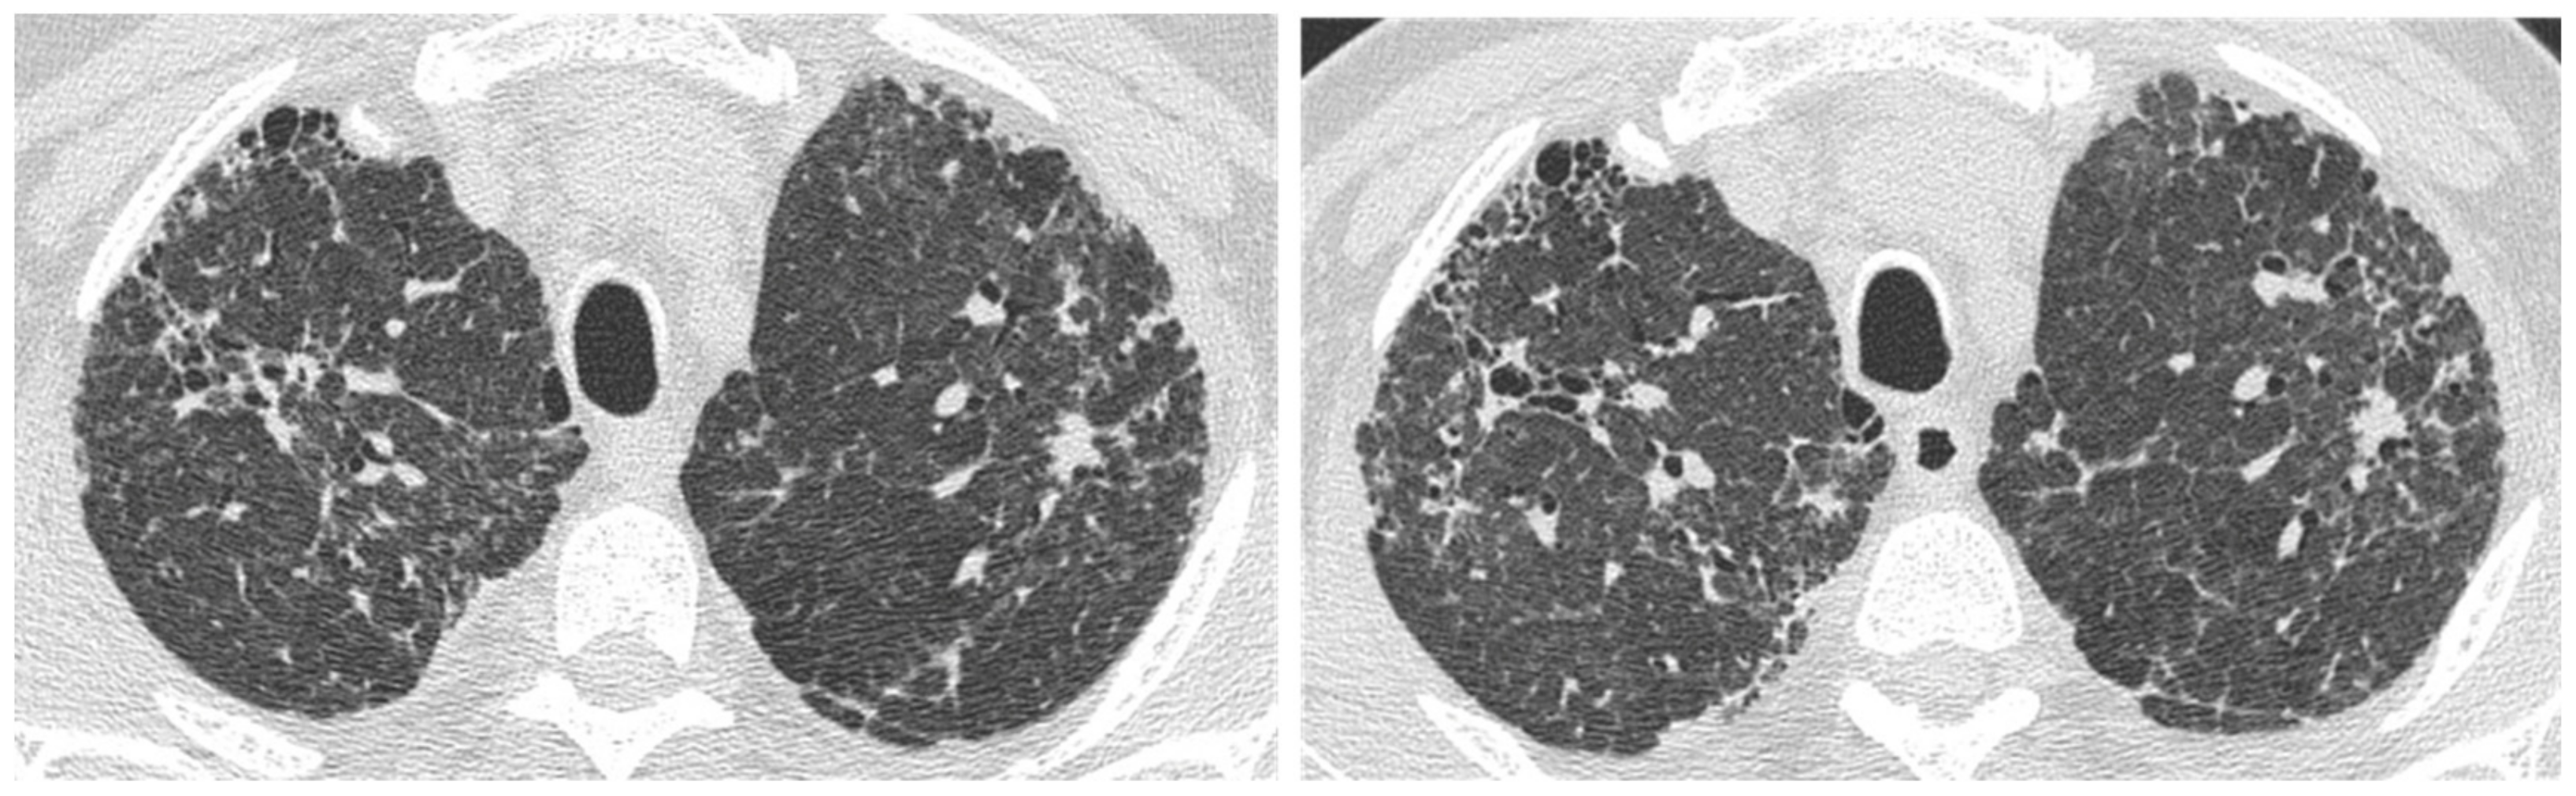

| Acute | Infections | Mycobacterium species | Peripheral mass-like lesion/subpleural nodules/segmental or lobar coalescent consolidation with or without necrotising cavitation. |

| Pneumocystis jirovecii | Ground glass opacity/no change from the baseline in a clinic context of infection. | ||

| Aspergillus | Fungal fronds in a pre-existing cavity in early stages. Subsequent coalescence of the cavity (air crescent sign). | ||

| Acute exacerbation IPF | New bilateral ground glass opacities and/or consolidation on a background of reticular or honeycombing pattern. | ||

| Right heart failure | Profuse septal thickening, ground glass opacities, pleural effusion on a background of reticular or honeycombing pattern. | ||

| Chronic | Lung cancer | Ill-defined rounded lesion, mimicking air space consolidation/nodular lesion developing within peripheral and basal honeycombing areas. Ground glass opacity in fibrosis area (mucinous bronchioloalveolar carcinoma). | |